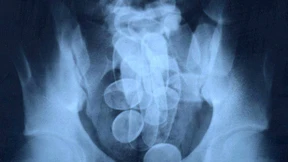

Ein junger Mann versteckt 130 Kokain-Beutelchen in seinem Magen. Mit dem Lohn für den Kurierdienst will er eine Operation bezahlen. Doch sein Plan geht schief. Jetzt muss er ins Gefängnis.